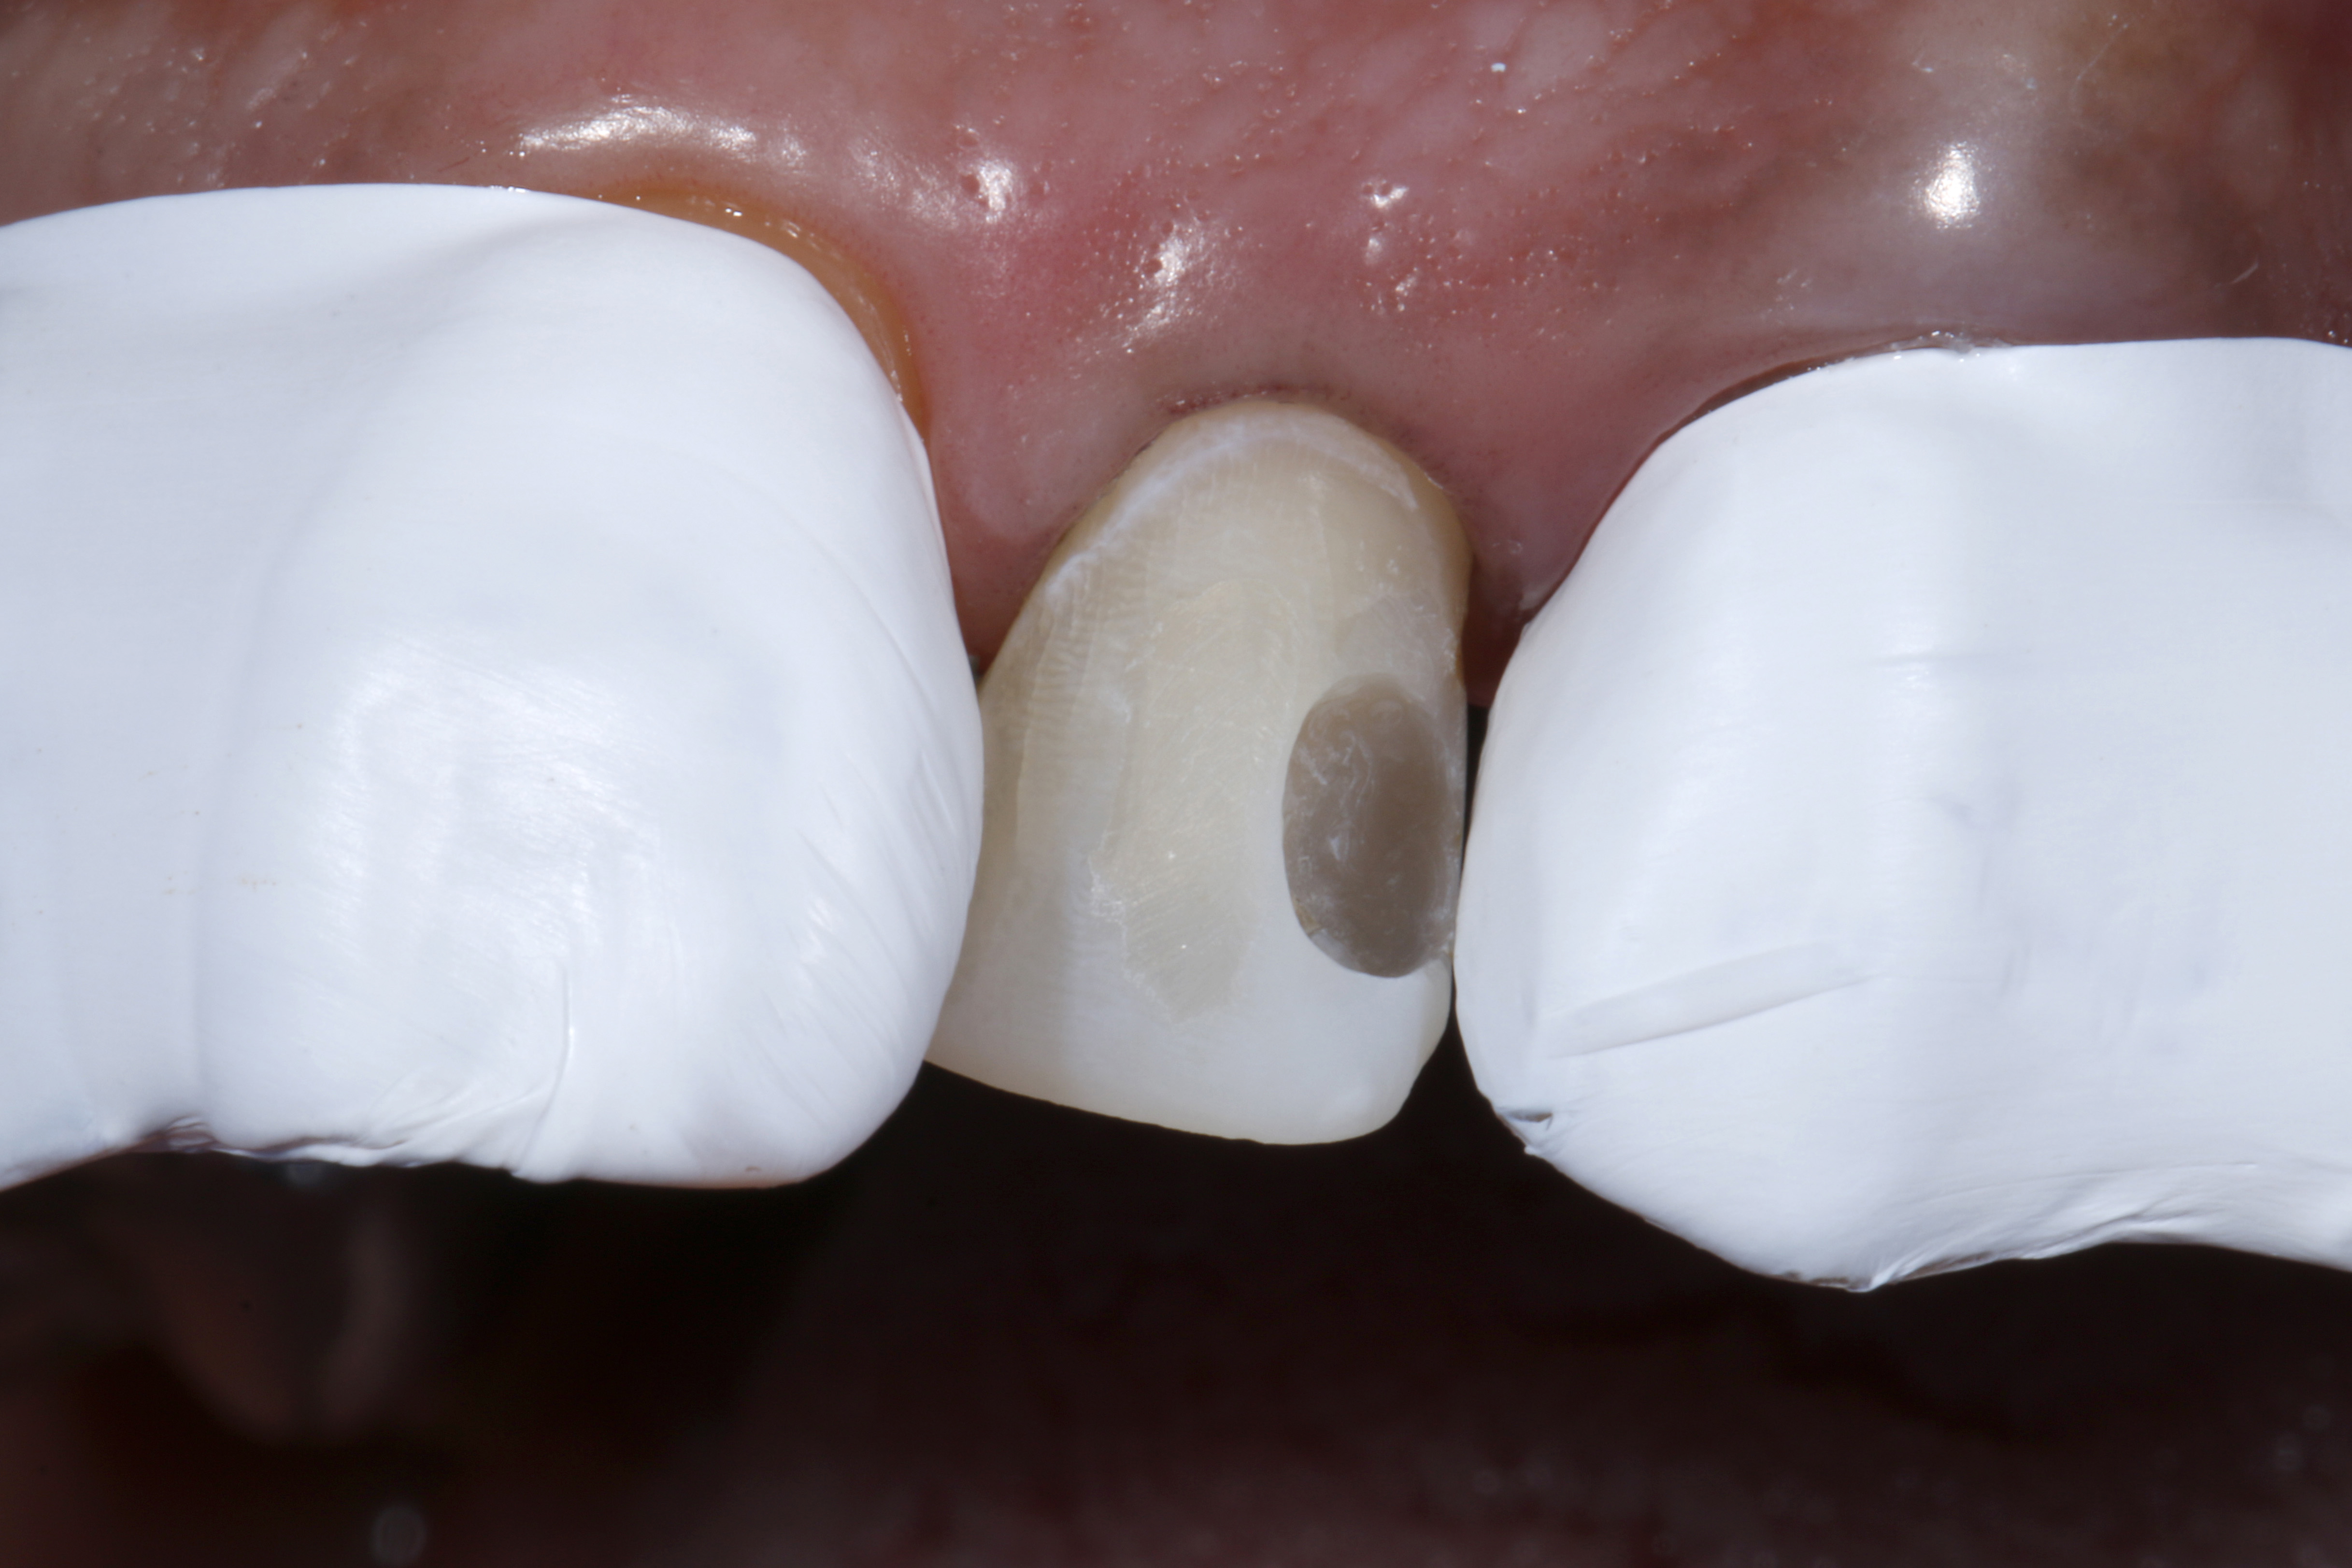

Do naszego gabinetu stomatologicznego zgłosiła się 60-letnia pacjentka z prośbą o lepsze optyczne ustawienie w łuku zębowym lewego bocznego siekacza szczęki, który jest wyraźnie położony podniebiennie w stosunku do lewego siekacza centralnego (ryc. 1 i 2).

Oprócz samego zęba, pacjentce szczególnie przeszkadzał fakt, że ząb wydawał się znacznie ciemniejszy w uśmiechu w porównaniu z lewym siekaczem centralnym i koroną PFM na lewym kle. Ząb bezzwłocznie zareagował nadwrażliwością na test na zimno, nie wykazał przy tym nieprawidłowości w teście opukiwania. Po zapoznaniu się z możliwymi alternatywami leczenia i ich kosztami, pacjentka zdecydowała się na licówkę bezpośrednią z użyciem uniwersalnego kompozytu GrandioSO Unlimited (VOCO GmbH, Cuxhaven).

Ryc. 1, 2. Sytuacja wyjściowa: lewy siekacz boczny jest ustawiony wyraźnie podniebiennie w stosunku do zębów sąsiednich. To przeszkadza pacjentce, który chciałaby uzyskać lepszą integrację wizualną z łukiem zębowym.

Ryc. 4. Usunięcie starego, dystalnego wypełnienia kompozytowego i niewielka preparacja powierzchni wargowej pod bezpośrednią licówkę kompozytową.